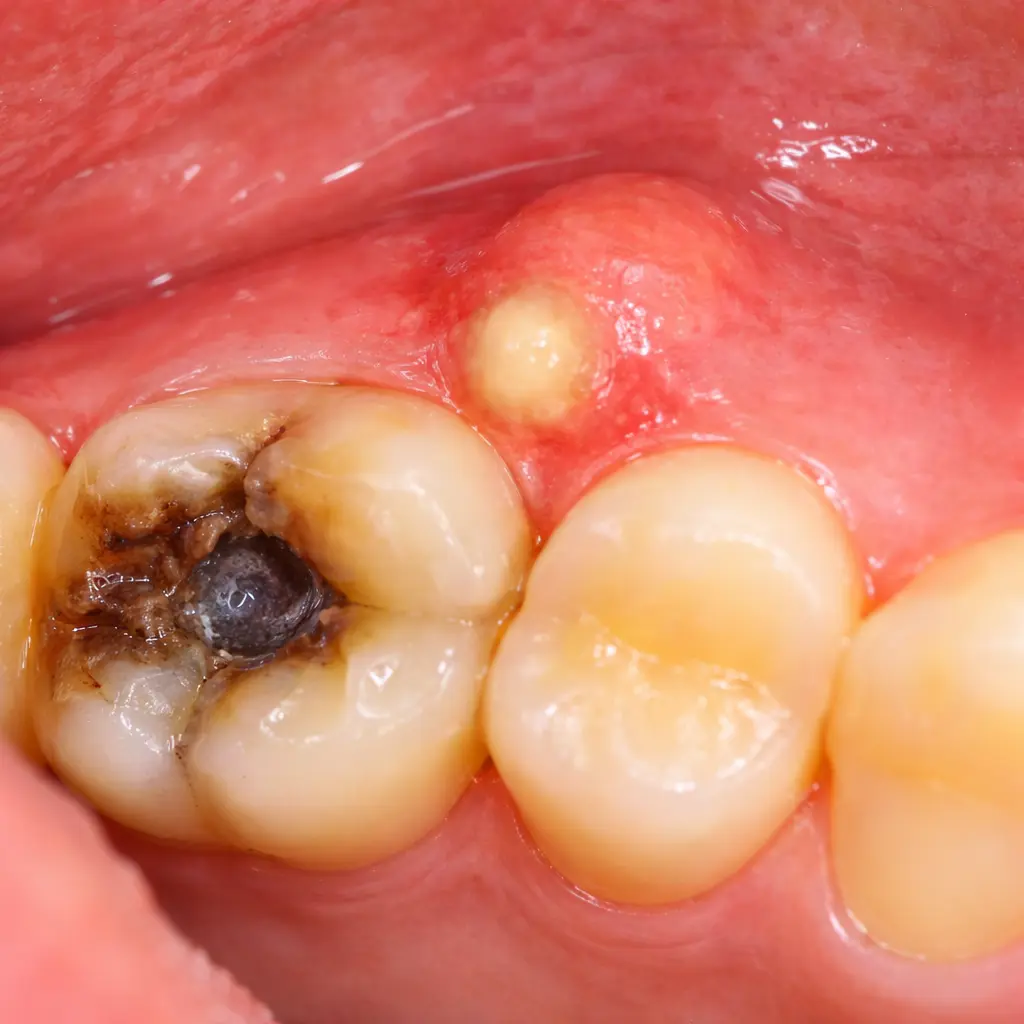

Gum swelling near one tooth

Tender or puffy gum around a specific tooth — especially if it keeps coming back — points to an abscess.

Pus or bad taste in mouth

A small pimple on the gum (fistula) means your body is draining a tooth infection. This is a dental emergency.

Swollen Gum Near One Tooth — Types of Dental Abscess Swelling

The gum near one tooth looks puffy or feels tender. Sometimes there is no pain — just visible swelling. This happens because bacterial infection leaks out through the root tip and your body sends immune cells to fight it. That battle shows up as swelling.

Pimple on the Gum, Bad Taste, or Pus — What a Dental Fistula Means

A small white or yellow bump on your gum near a specific tooth is called a dental fistula (or sinus tract). It is your body draining pus from a tooth abscess. When it drains, you may notice a bad taste or foul smell that appears and disappears.

“The pimple burst and the pain went away — I thought it healed by itself.”

The abscess drained, relieving pressure. The infection source inside the root is still active. Without root canal treatment, it will refill — often with more bone destruction each time.